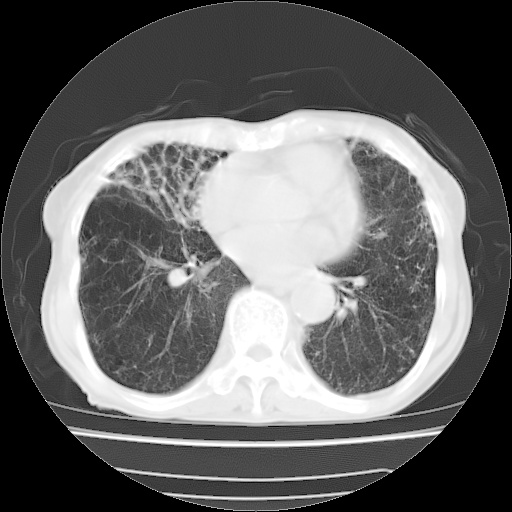

病人发热、气促就诊。原二周前已行ct扫描,当时诊断为双肺下叶、右肺中叶支气管扩张并感染,双肺上叶片状渗出性病变。今天复查胸部ct,双肺下叶支气管扩张并感染病灶较前明显吸收,但双肺上叶渗出性病变较范围较前明显增大。

现传今天ct图像给大家讨论。

双肺多发大片状、斑片状高密度渗出影,部分实变,考虑病毒性肺炎。